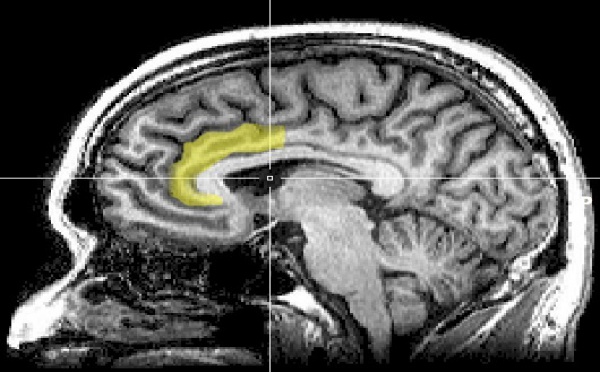

Una síntesis de 18 investigaciones basadas en técnicas de neuroimagen, realizada por especialistas de la Universidad de Nueva York (NYU), en Estados Unidos, ha revelado que el cerebro humano utiliza los mismos circuitos neuronales tanto para juzgar a una persona por motivos étnicos como para procesar emociones o tomar decisiones.